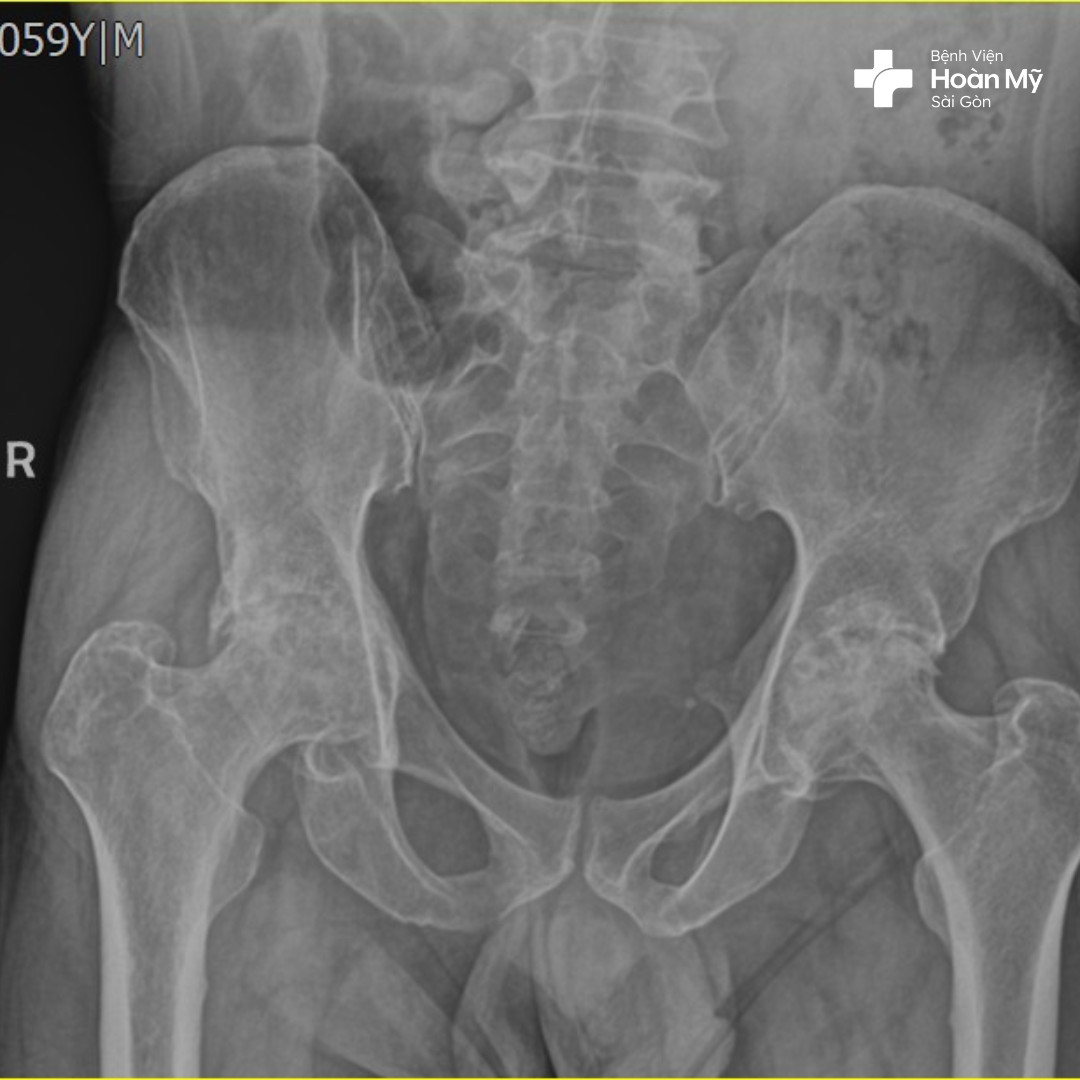

Hình ảnh X-quang trước khi phẫu thuật của người bệnh

Thoái hóa khớp háng

Thoái hoá khớp háng là một trong những nguyên nhân hàng đầu gây ra cơn đau khớp háng, tỷ lệ mắc thoái hóa khớp sẽ tăng dần theo tuổi tác và thời gian.

Tình trạng này lâu dần sẽ gây mất và tổn thương sụn khớp, khiến cho việc cử động bị hạn chế và gây đau đớn. Người bệnh xuất hiện các cơn đau nặng do bệnh thoái hóa khớp và không thể thực hiện các hoạt động bình thường. Thậm chí chỉ ngồi không di chuyển cũng có thể cảm nhận cơn đau gây khó khăn trong đi lại và sinh hoạt.

Hoại tử vô mạch chỏm xương đùi

Tình trạng này xảy ra khi nguồn máu cung cấp cho xương bị gián đoạn khiến cho các mô xương bị hoại tử. Dần dần các ổ xương bị khuyết hổng khiến cho phần sụn và xương bị phá hủy. Bệnh nhân gặp tình trạng này sẽ có cảm giác đau phần khớp háng và khó khăn khi xoay người.

- Thoái hóa khớp: Thường được gọi là viêm khớp do hao mòn, viêm xương khớp làm tổn thương lớp sụn trơn bao phủ các đầu xương và giúp các khớp cử động trơn tru.

- Viêm khớp dạng thấp: Gây ra bởi hệ thống miễn dịch hoạt động quá mức, viêm khớp dạng thấp tạo ra một loại viêm có thể ăn mòn sụn và đôi khi là xương bên dưới, dẫn đến các khớp bị tổn thương và biến dạng.

- Hoại tử xương: Nếu không có đủ máu cung cấp cho phần bóng của khớp hông, chẳng hạn như có thể do trật khớp hoặc gãy xương, xương có thể bị xẹp và biến dạng.